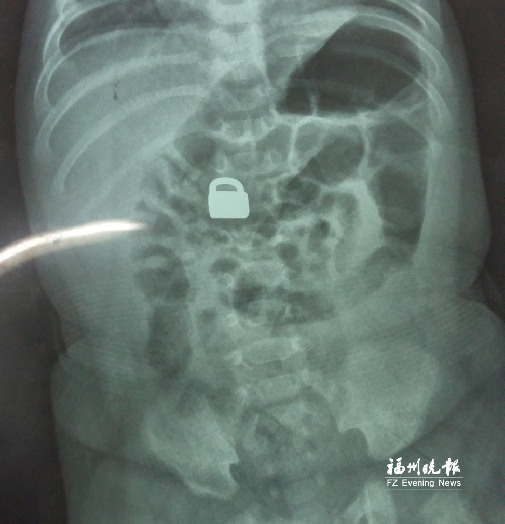

7.25龍巖當(dāng)?shù)蒯t(yī)院拍的X光片顯示,平安鎖在寶寶體內(nèi)。

這名60天大的“神奇寶寶”來(lái)自龍巖,哥哥也只有兩歲。7月25日,兄弟倆的媽媽突然發(fā)現(xiàn)寶寶胸前掛著的平安鎖不見(jiàn)了,便問(wèn)小哥哥是否看到弟弟的平安鎖。小哥哥回答,他把平安鎖塞到弟弟嘴里了。媽媽趕緊檢查寶寶嘴巴,沒(méi)有發(fā)現(xiàn)平安鎖。雖然寶寶沒(méi)有任何癥狀,但媽媽還是帶著他去當(dāng)?shù)蒯t(yī)院檢查。拍片結(jié)果顯示,平安鎖真的在寶寶體內(nèi)。

“X光片顯示,那是一把1.5厘米×0.9厘米的平安鎖,有指甲蓋大小,已經(jīng)到了寶寶的小腸處?!?月28日,陳惠萍見(jiàn)到寶寶時(shí),吃了一驚,“他真的好小,被抱在媽媽?xiě)牙铮劬ξ⑽⒈犻_(kāi),我估計(jì)他的世界還是混沌的,沒(méi)想到就已經(jīng)接受了這么大的挑戰(zhàn)?!?/p>